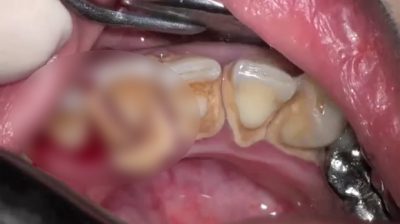

Čišćenje zuba sa kamenim veliki problem

Zubar u Japanu zapisima uklanjanje Tartar od pacijenta, који нису посетили зубара за осам година. Slejt (masu od mikroba.) zubi mogu biti pretvoren u kamen, tvrdom materijalu koji se mogu ukloniti samo sa profesionalno čišćenje zubar.

Kada se formirao kamen, pranje zuba i čišćenje između zuba postaje teže, i desni mogu super ili iskrvari. Ovo stanje se naziva gingivitis, Rana faza bolesti desni. Čišćenje koncem pomaže u odstranjivanju zubnog plaka, smanjujući mogućnost desni bolesti i kvarenja zuba.